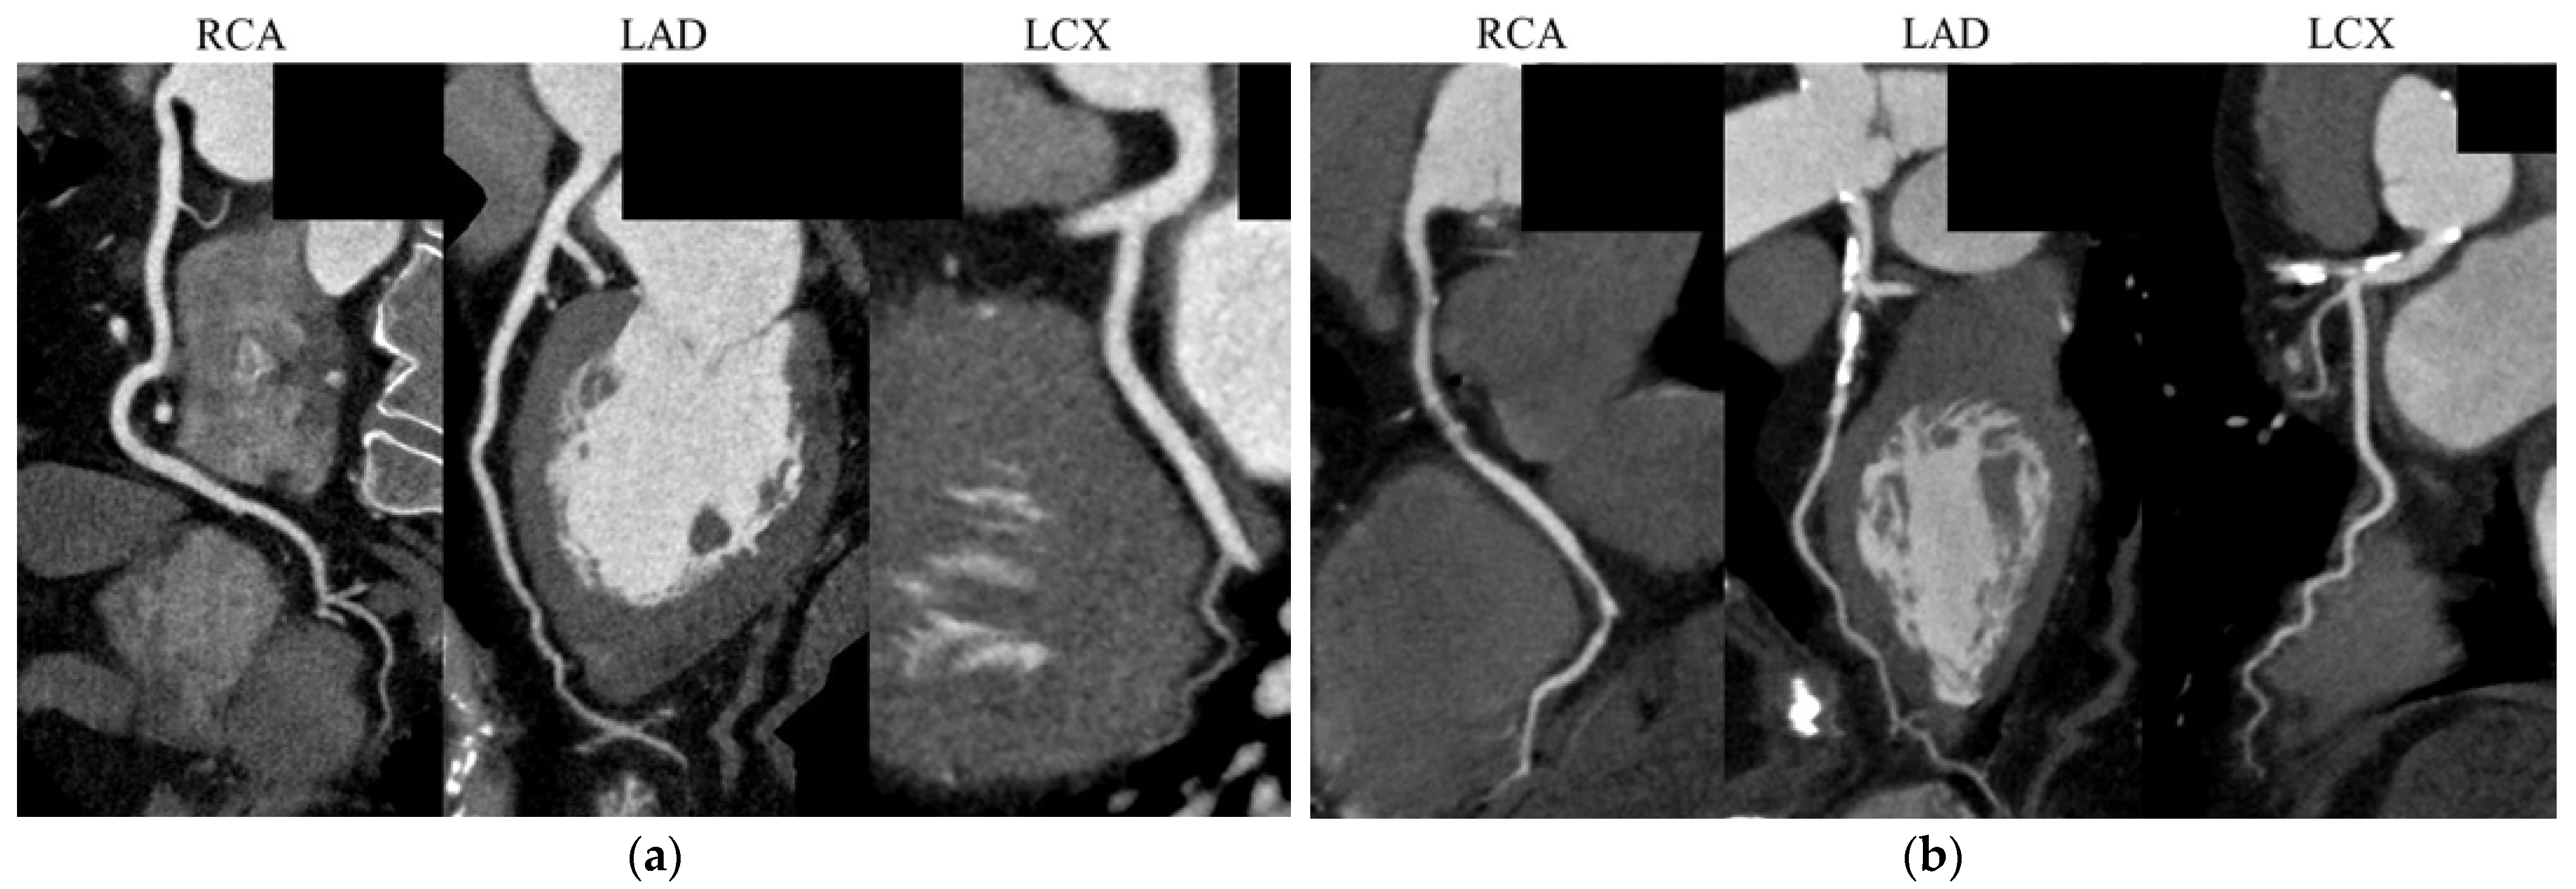

- Ropers, D.; Rixe, J.; Anders, K.; Küttner, A.; Baum, U.; Bautz, W.; Daniel, W.G.; Achenbach, S. Usefulness of multidetector row spiral computed tomography with 64-x 0.6-mm collimation and 330-ms rotation for the noninvasive detection of significant coronary artery stenoses. Am. J. Cardiol. 2006, 97, 343–348. [Google Scholar] [CrossRef]

- Shiga, Y.; Miura, S.; Mitsutake, R.; Kawamura, A.; Uehara, Y.; Saku, K. Significance of serum high-density lipoprotein cholesterol levels for diagnosis of coronary stenosis as determined by MDCT in patients with suspected coronary artery disease. J. Atheroscler. Thromb. 2010, 17, 870–878. [Google Scholar] [CrossRef] [PubMed]

- Mitsutake, R.; Miura, S.; Shiga, Y.; Uehara, Y.; Saku, K. Association between hypertension and coronary artery disease as assessed by coronary computed tomography. J. Clin. Hypertens. 2011, 13, 198–204. [Google Scholar] [CrossRef] [PubMed]

- Ueda, Y.; Shiga, Y.; Idemoto, Y.; Tashiro, K.; Motozato, K.; Koyoshi, R.; Kuwano, T.; Fujimi, K.; Ogawa, M.; Saku, K.; et al. Association Between the Presence or Severity of Coronary Artery Disease and Pericardial Fat, Paracardial Fat, Epicardial Fat, Visceral Fat, and Subcutaneous Fat as Assessed by Multi-Detector Row Computed Tomography. Int. Heart J. 2018, 59, 695–704. [Google Scholar] [CrossRef]

- Shiga, Y.; Tashiro, K.; Miura, E.; Higashi, S.; Kawahira, Y.; Kuwano, T.; Sugihara, M.; Miura, S.I. Association Between Major Adverse Cardiovascular Events and the Gensini Score or Coronary Artery Calcification Score in Hypertensive Patients Who Have Undergone Coronary Computed Tomography Angiography. Cardiol. Res. 2023, 14, 91–96. [Google Scholar] [CrossRef]

- Ohnishi, N.; Shiga, Y.; Tashiro, K.; Kawahira, Y.; Shibata, Y.; Inoue, H.; Morii, J.; Nishikawa, H.; Kato, Y.; Kuwano, T.; et al. Association between major adverse cardiovascular events and pentraxin-3 in patients who have undergone coronary computed tomography angiography: From the FU-CCTA registry. Heart Vessel. 2023, 38, 309–317. [Google Scholar] [CrossRef]

- Kawahira, Y.; Shiga, Y.; Inoue, H.; Suematsu, Y.; Tashiro, K.; Kato, Y.; Fujimi, K.; Takamiya, Y.; Kuwano, T.; Sugihara, M.; et al. Association between high-density lipoprotein cholesterol levels and major adverse cardiovascular events in patients who underwent coronary computed tomography angiography: FU-CCTA registry. Heart Vessel. 2021, 36, 1457–1465. [Google Scholar] [CrossRef]